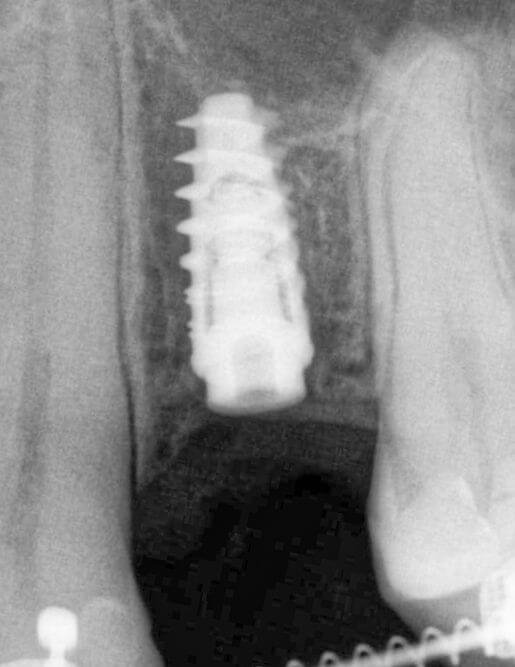

Імплантація - це метод вживлення імплантату (штучного кореня) у верхню або нижню щелепу.Такий штучний корінь виготовляється з спеціального сплаву, що надійно вживлюється в кістку та стає надійною опорою, на яку встановлюється коронка.

Більшість імплантів виготовляється з медичного титану. Він біосумісний, не викликає жодних реакцій та відмінно вростає в кістку щелепи.

Команда Космічної стоматології Драганчука - фанати якості та інноваційних технологій, тому обираємо імпланти кореня зуба з титану та його сплавів, зокрема Roxolid. Цей космічний сплав складається з титану та цирконію й має підвищену міцність (+30%). Це дозволяє використовувати імпланти особливо маленьких розмірів та уникнути додаткового нарощення кістки.